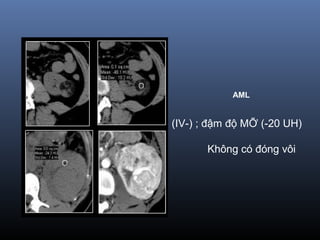

(IV-) ; đậm độ MỠ (-20 UH)

Không có đóng vôi

AML